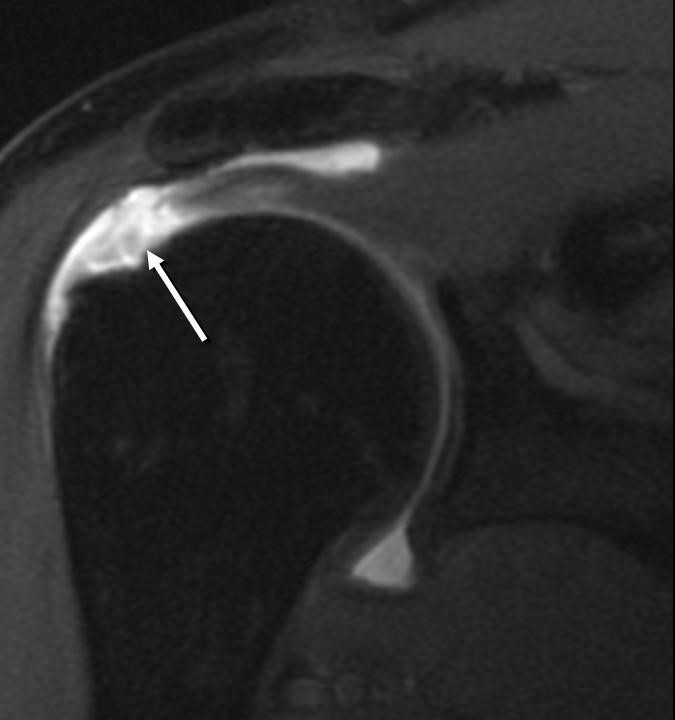

Hình 4. Hình ảnh tổn thương gân cơ trên gai

Hình ảnh điển hình tổn thương GCX